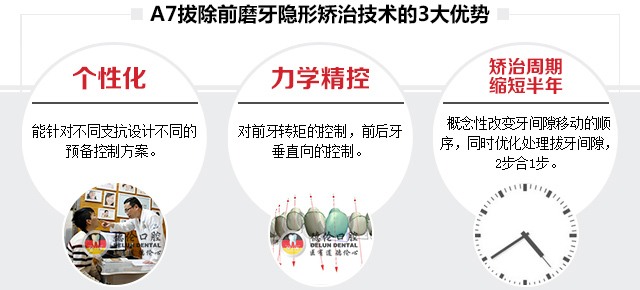

- 以往骨性错颌畸形和拔除前磨牙的高疑难症状还停留在用钢丝固定矫治的阶段,如今A6、A7技术通过隐形牙套也可很好的解决这类症状,让青少年骨性功能性矫治和成人疑难错颌畸形矫治变得高效、美观、舒适。